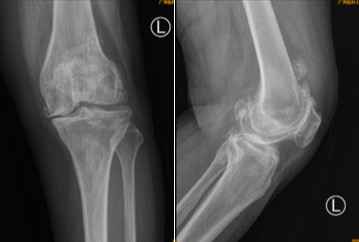

术前X光检查显示何阿姨左膝关节软骨完全磨损,髌上囊及股骨后髁大量骨赘增生,何阿姨尽管行动不便、疼痛难忍,却对手术顾虑较大。“如果不进行手术根治,日后不但难以行走,更会因为长期不运动,使得心肺功能下降,原有的高血压、糖尿病等基础疾病也难以控制。”张弛分析了手术的必要性和有效性,最终患者和家属一致决定进行手术,但手术的难题却也如同“拦路虎”一样出现。

术前X光片提示患者左膝关节软骨完全磨损,髌上囊及股骨后髁大量骨赘增生。

术中运用后交叉韧带保留型的假体进行膝关节表面置换,术后复查照片精准复制了人工智能测量的结果。